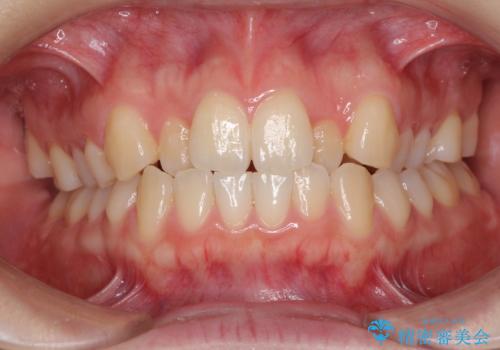

前歯のクロスバイトをインビザライン矯正で改善

- 前歯のデコボコと上下のクロスバイトを気にして来院された患者様です。

インビザラインを用い、IPR(歯と歯の間を削る)と歯列全体を拡大させることで、歯並びを整えていくこととしました。

上の前歯が下の前歯を乗り越える際、奥歯がほとんど咬めない時期があり、乗り越えた後も、インビザライン特有の奥歯の咬みにくさが続きました。

咬み合わせ改善のために治療期間を要しましたが、最終的に奥歯はしっかりと咬めるようになりました。